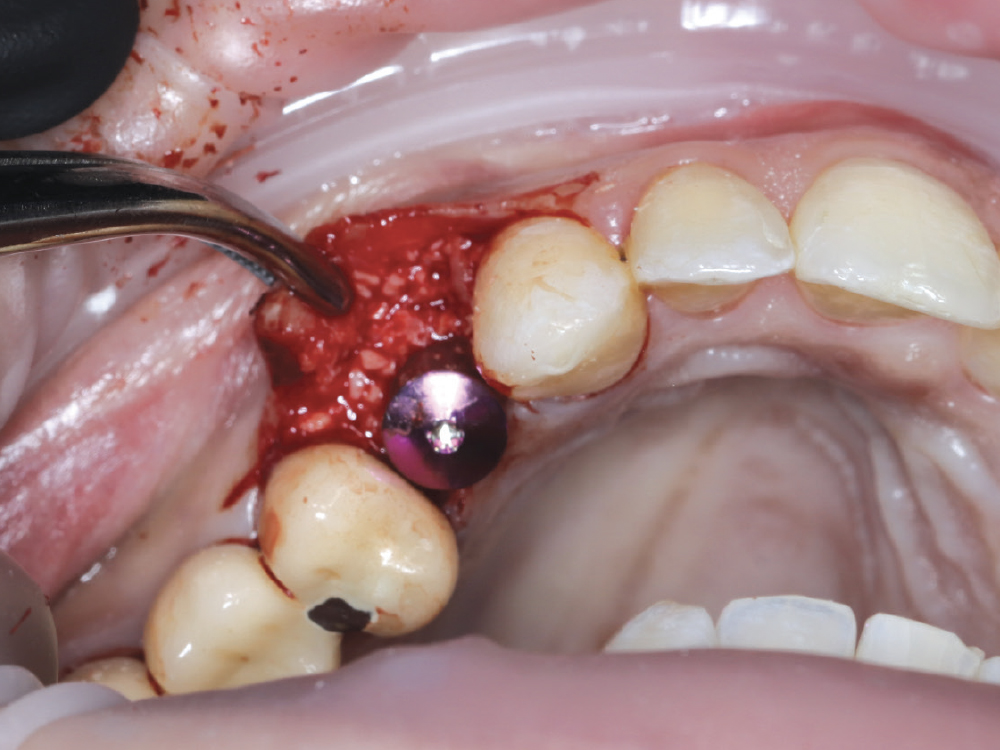

At site #12, the buccal plate was found to be thin and deficient, necessitating simultaneous grafting

Figure 6: At site #12, the buccal plate was found to be thin and deficient, necessitating simultaneous grafting. Allograft was placed to restore the buccal contour and covered with a collagen membrane to stabilize the graft and support hard- and soft-tissue regeneration. The combination of guided precision and immediate augmentation ensured optimal implant positioning and ridge preservation. The total surgical time for both implants, including grafting and membrane placement, was approximately one hour.

Allograft was placed to restore the buccal contour and covered with a collagen membrane to stabilize the graft and support hard- and soft-tissue regeneration